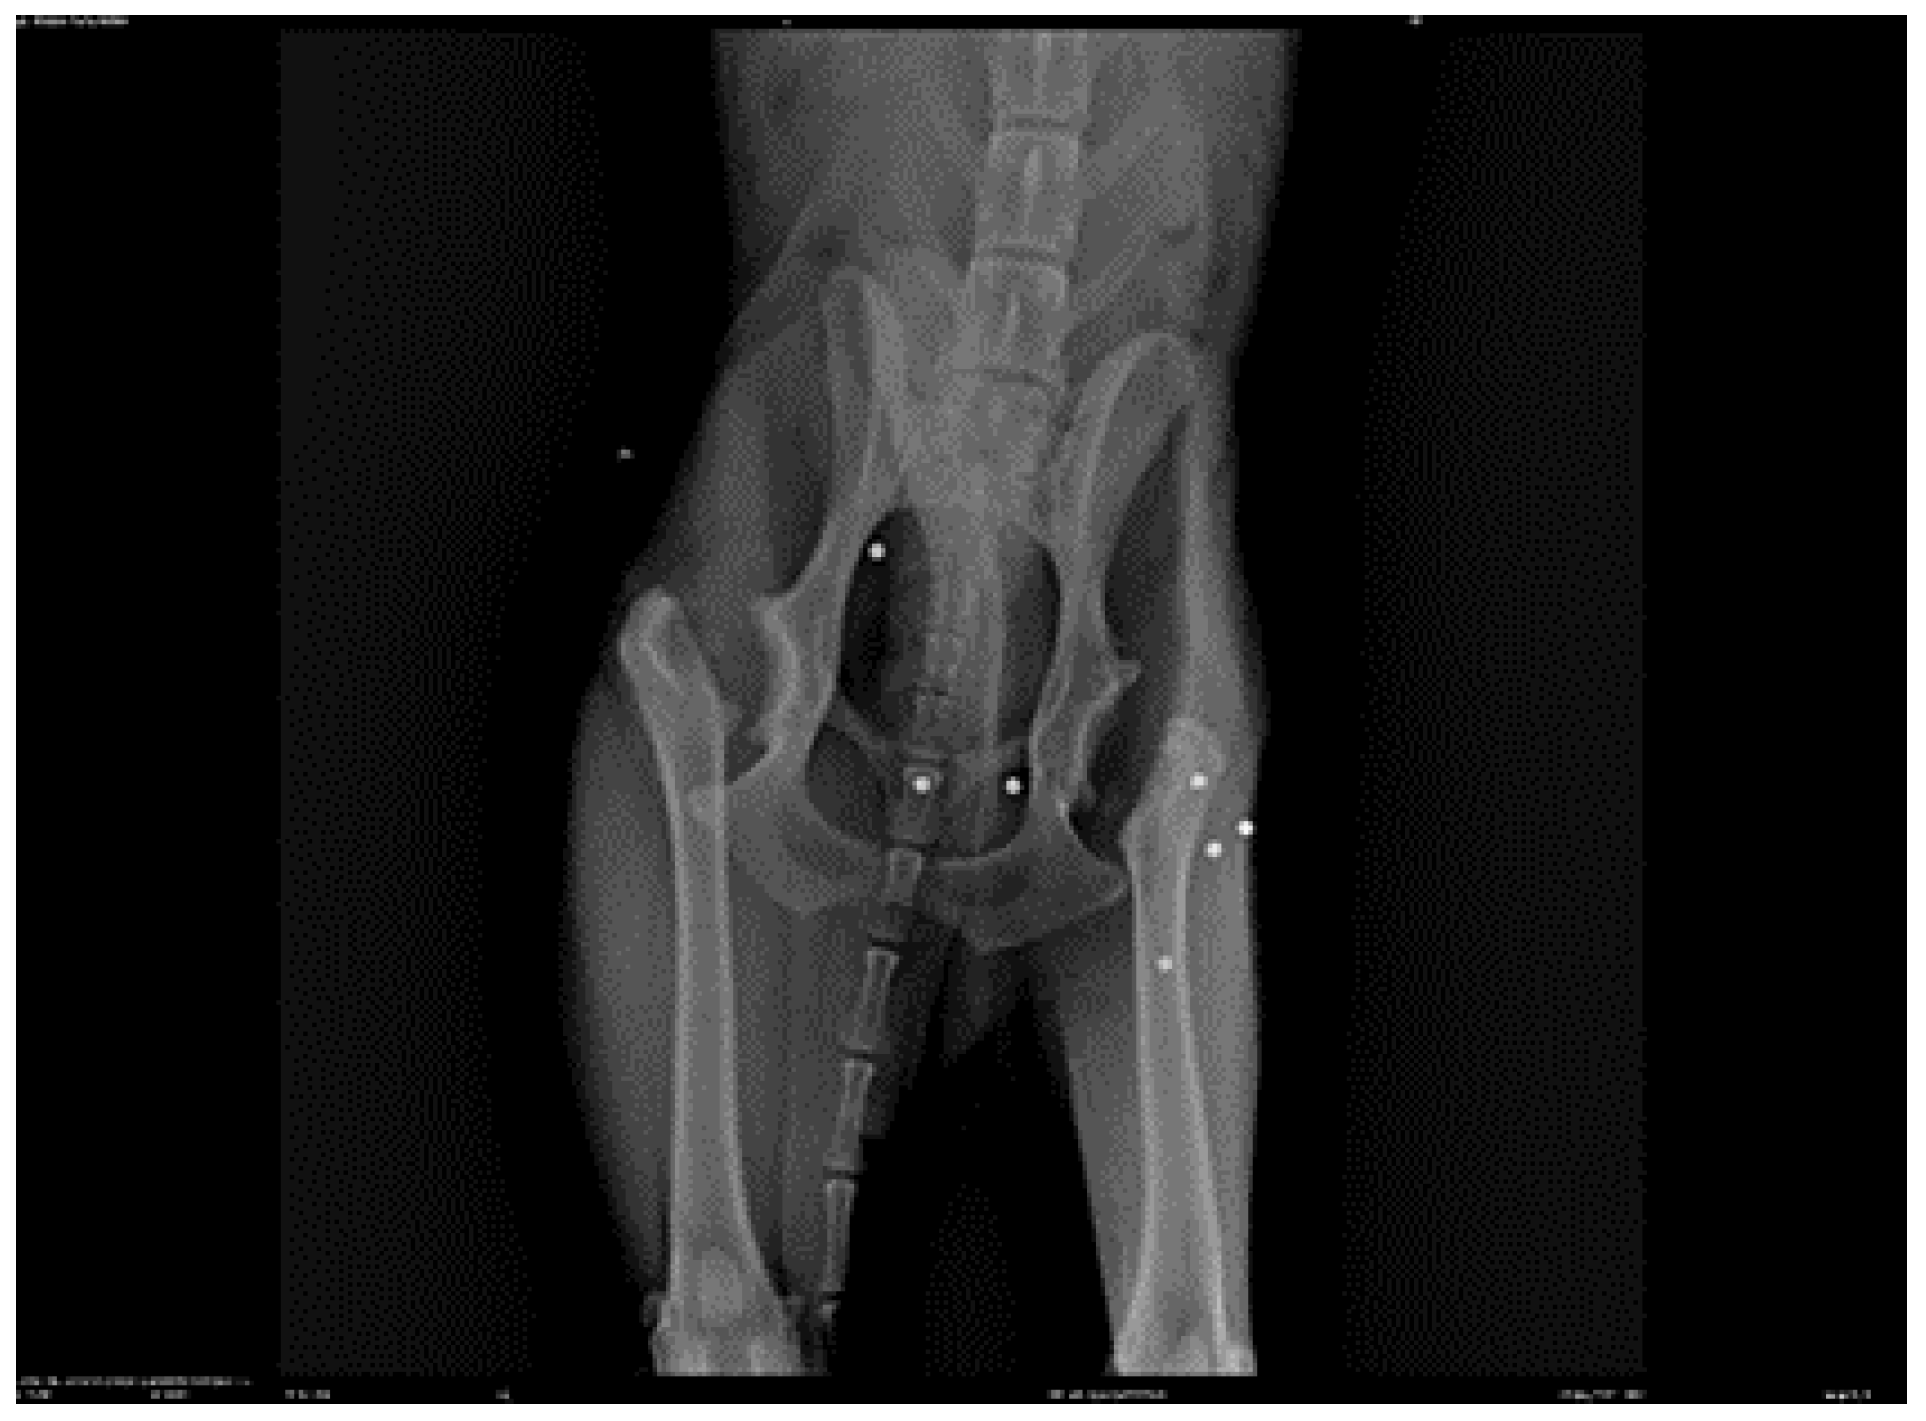

![]() |